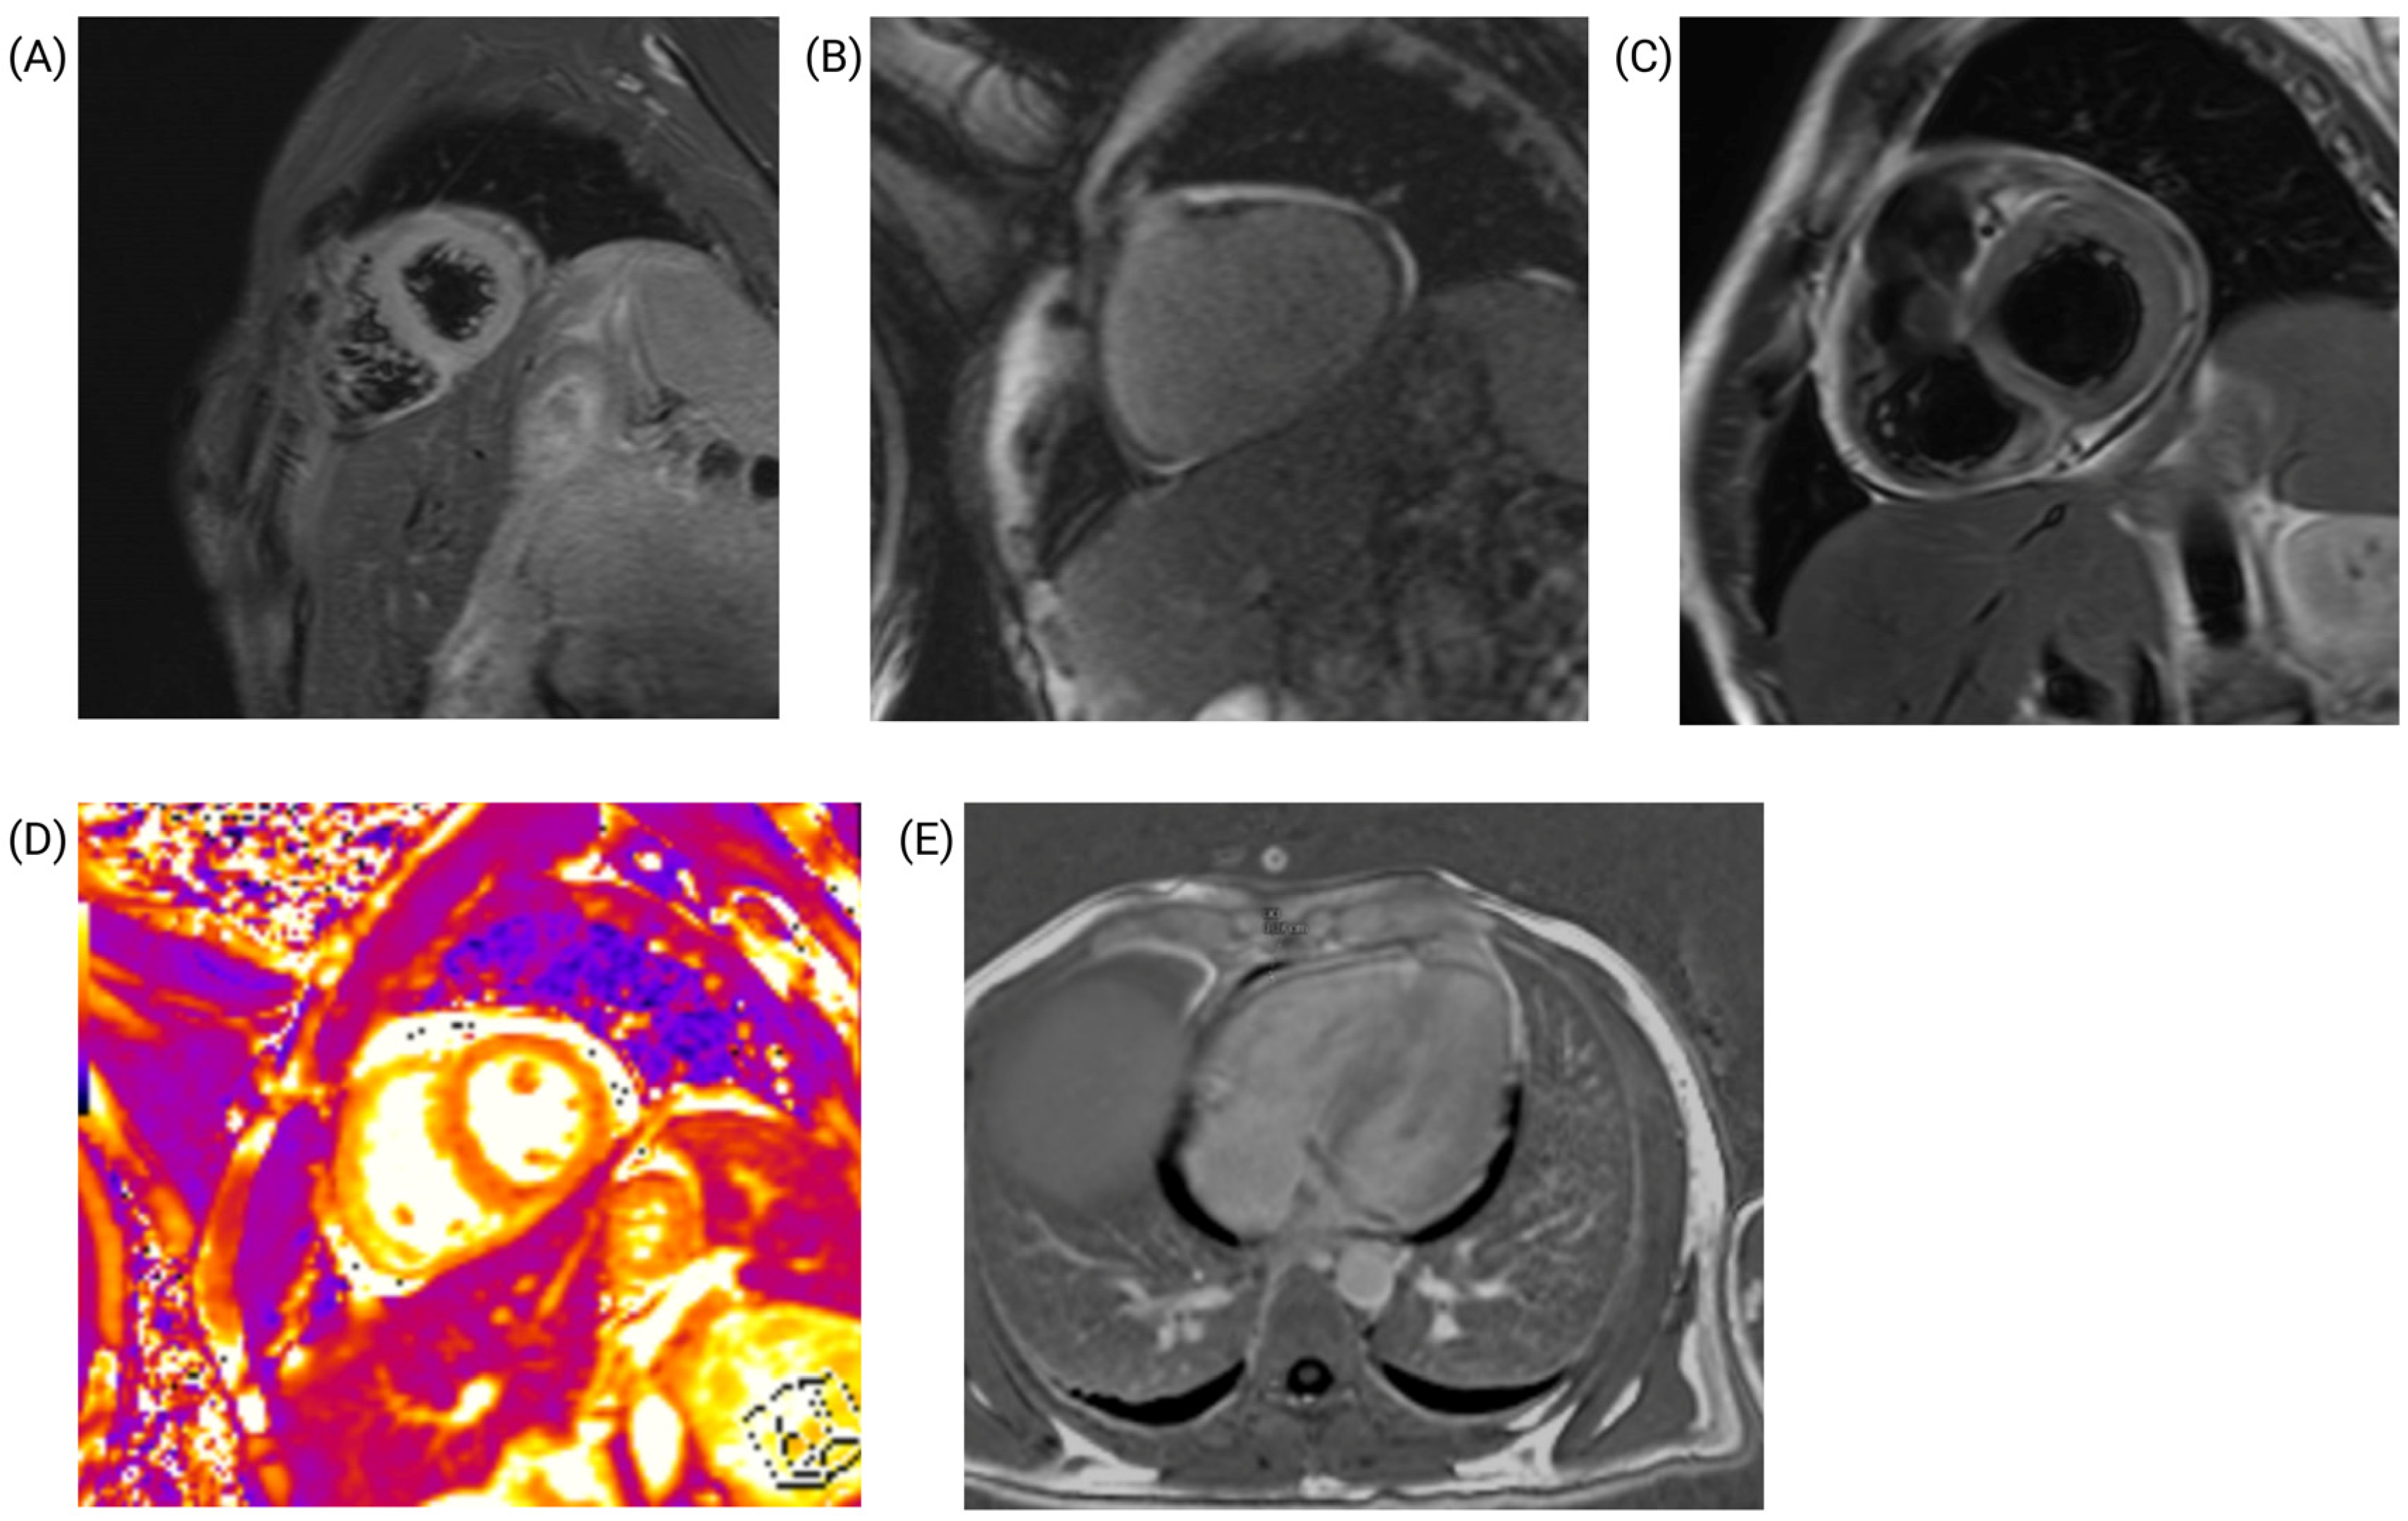

Cardiac magnetic resonance imaging (MRI) confirmed the presence of myopericarditis (Figure 5). Nonsteroidal anti-inflammatory drugs (ibuprofen), were initiated, leading to partial relief of chest pain. Concurrently, a biopsy of cervical adenopathy revealed nonspecific necrotizing suppurative lymphadenitis. The patient’s Systemic Lupus Erythematosus Disease Activity Index (SLEDAI) score was 19, indicating severe systemic disease activity.

Endomyocardial biopsy (EMB) remains the gold standard for diagnosing myocarditis; however, its invasive nature, risks, and limited availability often restrict its use to severe or life-threatening cases [13]. Noninvasive imaging modalities, particularly cardiac magnetic resonance imaging (CMRI), are now the preferred diagnostic tools. CMRI enables tissue characterization and detects critical changes, such as myocardial edema, necrosis, and fibrosis, which are hallmarks of lupus myocarditis [17,18,19]. In our patient, CMRI confirmed the diagnosis of myopericarditis and played a pivotal role in assessing the extent of myocardial involvement.

Figure 5. Cardiac magnetic resonance imaging findings. (A) T2-STIR (short axis) showing edema and inflammation in the cardiac apex. (B) Late gadolinium enhancement (sagittal view, short axis) showing pericardial thickening measuring approximately 5 mm. (C) T2-STIR (short axis) showing pericardial thickening. (D) T2 map (short axis) showing pericardial thickening measuring approximately 5 mm. (E) Late gadolinium enhancement (four-chamber, axial-view, long-axis) showing pericardial thickening and effusion.